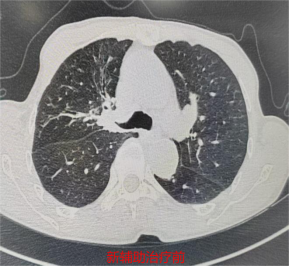

辅助治疗后影像图。宁德市医院供图

3月10日,胸心外科副主任医师颜海强带领团队为林先生实施胸腔镜下右肺上叶切除+支气管成形+肺门纵隔淋巴清扫术。术中发现,肿瘤紧邻支气管开口,且经新辅助治疗后,肿瘤区域纤维化严重,血管与支气管致密粘连,解剖结构复杂,手术难度及风险较高。手术团队凭借精湛的微创操作技巧,精细分离粘连组织,精准保护重要血管、神经,成功将肿瘤完整切除,术中冰冻病理提示支气管残端阴性,保障了手术根治效果。